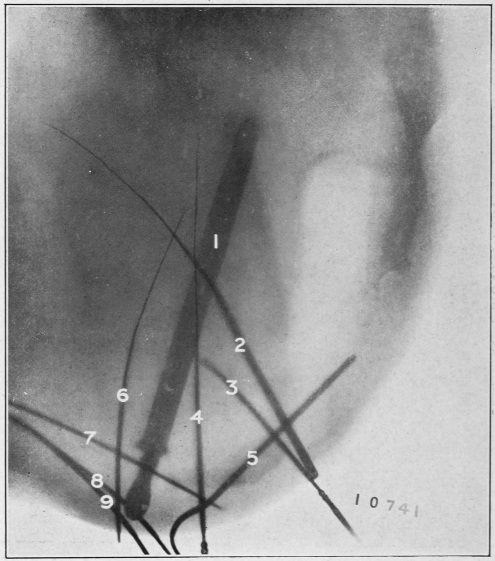

Nine Radiograph Illustrations Showing Mucus Channels and Cavities200